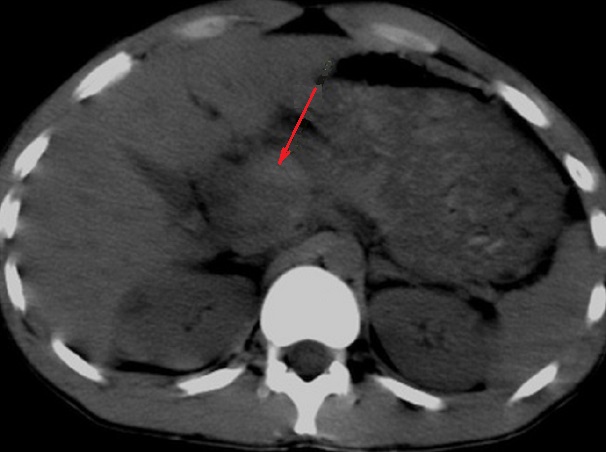

Image radiologique TDM

d'une traumatisne du pancreas avec aspect

lesionnel d'elargi volumineuse heterogene et a

hypodense de la tete du pancreas ( fleche rouge ) .

Coupe axiale TDM non contrast intraveineuse |